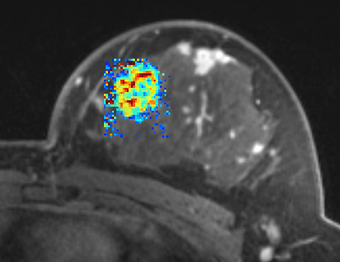

PkModeling (Pharmacokinetics Modeling) calculates quantitative parameters from Dynamic Contrast Enhanced DCE-MRI images. This module performs two operations:

- estimation of quantitative perfusion parameters from DCE MRI

- treatment response evaluation

- breast, prostate, brain DCE MRI analysis

- Output Ktrans image (OutputKtransFileName): Output volume transfer constant between blood plasma and EES (extracellular-extravascular space) at each voxel.

- Output ve image (OutputVeFileName): Output fractional volume for extracellular space at each voxel.

- Output AUC image (OutputAUCFileName): Output area under the curve (AUC) of each voxel, measured from bolus arrival time to the end time of interval, normalized by the AUC of the AIF.